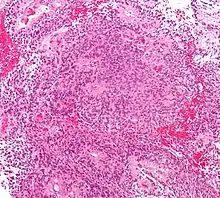

Lymphomes primitifs du SNC

Le lymphome primitif du système nerveux central représente environ 2 pour cent à 3 pour cent de toutes les tumeurs cérébrales chez les patients ayant un système immunitaire normal. Ils surviennent plus fréquemment chez les hommes de plus de 55 ans jusqu'à 60 ans. Près de la moitié de tous les lymphomes surviennent chez des patients de plus de 60 ans et environ un quart chez des patients de plus de 70 ans. L'incidence semble augmenter avec l'âge, mais la raison n'est pas encore claire. Les patients dont le système immunitaire est affaibli sont plus à risque de développer un lymphome du SNC, de sorte que ceux qui ont subi une greffe d'organe ont une immunodéficience congénitale ou une maladie auto-immune, ou sont infectés par le virus de l'immunodéficience humaine. Les lymphomes cérébraux associés au VIH sont associés au virus d'Epstein-Barr, en particulier chez les patients dont le nombre de lymphocytes CD4 est inférieur à 500 cellules par millimètre cube dans le sang. La plupart des lymphomes du SNC sont des lymphomes diffus à grandes cellules B.

Les patients souffrent d'une variété de symptômes caractéristiques d'une lésion massive focale ou multifocale. L'IRM montre généralement des tumeurs avec un rehaussement de contraste homogène au sein de la substance blanche périventriculaire profonde. La multifocalité et le rehaussement inhomogène sont typiques des patients dont le système immunitaire est affaibli. L'analyse du lymphome du SNC est extrêmement importante dans le diagnostic différentiel de la néoplasie cérébrale. Il est à noter que l'administration de corticoïdes peut entraîner la disparition complète du rehaussement, rendant difficile le diagnostic des lésions. Par conséquent, si un lymphome du SNC doit être pris en compte dans le diagnostic différentiel, les corticoïdes doivent être évités à moins que l'effet de masse ne provoque un problème grave et immédiat chez le patient.

La biopsie de la lésion suspectée est cruciale. Contrairement au lymphome systémique à grandes cellules B, dans lequel la chimiothérapie et la radiothérapie sont efficaces et le traitement des lésions localisées est curatif, le lymphome du système nerveux central répond généralement au traitement initial mais réapparaît ensuite. Comme pour le lymphome systémique, le rôle de la chirurgie est principalement limité à l'obtention d'échantillons de tissus appropriés pour le diagnostic.